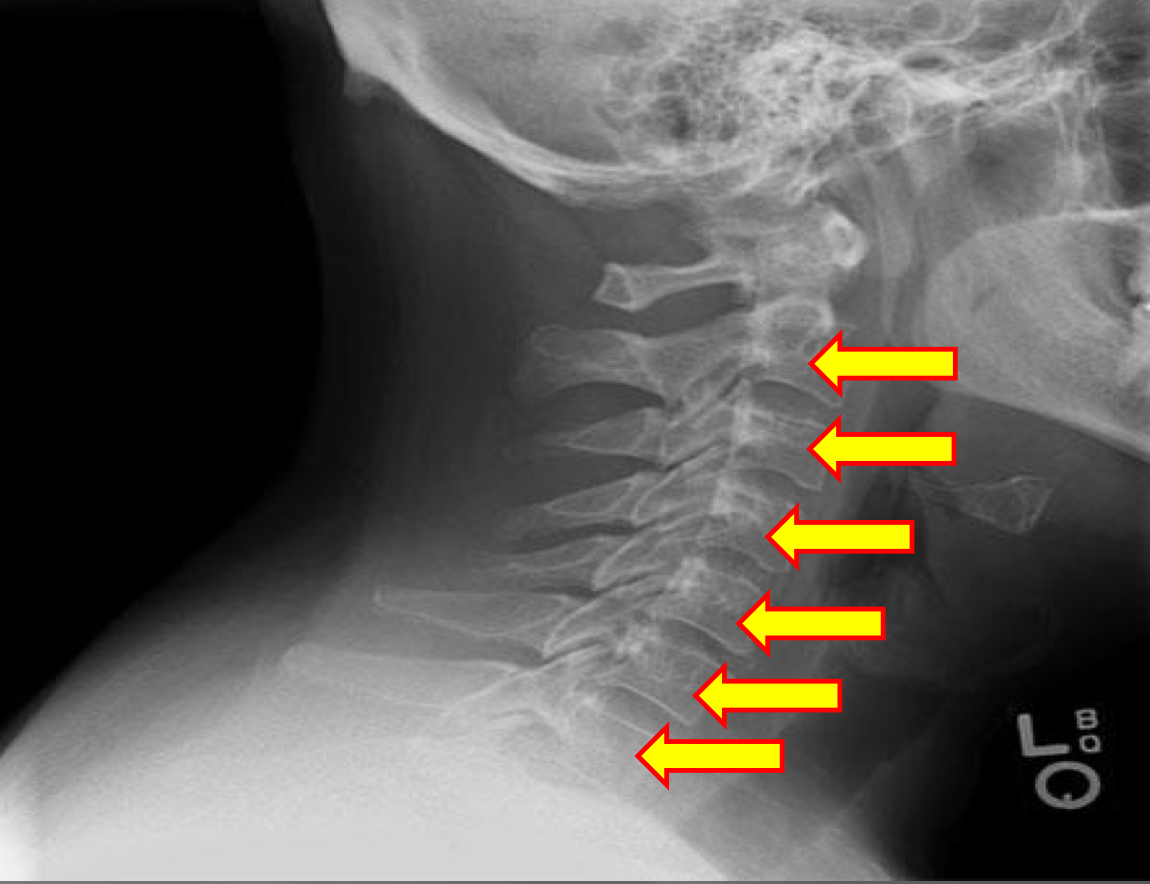

What view is this?

Lateral Cervical

What is this?

Vertebral Bodies

What is this?

Superior and Inferior Endplate Tips

What is this?

Disc space